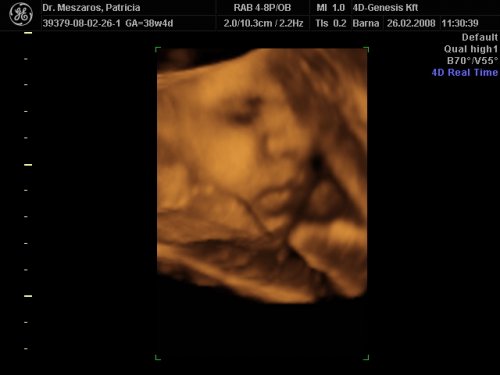

A doki szerint pufók kislány